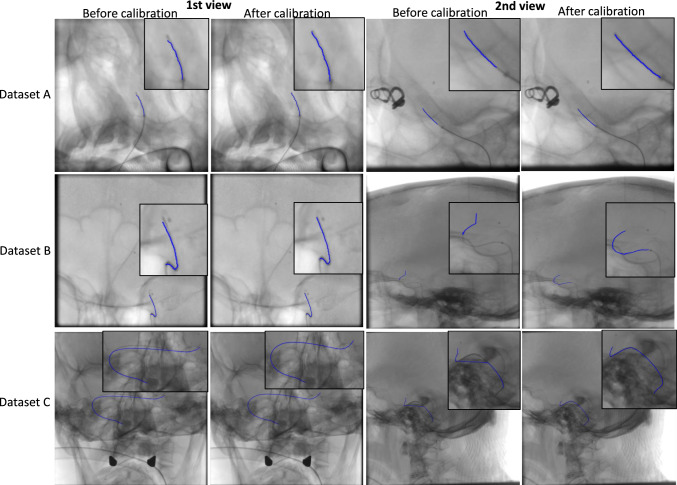

Methods: We propose an online calibration method using image-specific features derived from interventional devices like guidewires and catheters (In the remainder of this paper, the term"catheter" will refer to both catheter and guidewire). The process begins with gantry-recorded data, refined through iterative nonlinear optimization. A machine learning approach detects and segments elongated devices by identifying candidates via thresholding on a weighted sum of curvature, derivative, and high-frequency indicators. An ensemble classifier segments these regions, followed by post-processing to remove false positives, integrating vessel maps, manual correction and identification markers. An interpolation step filling gaps along the catheter.

Results: Among the optimized ensemble classifiers, the one trained on the first frames achieved the best performance, with a specificity of 99.43% and precision of 86.41%. The calibration method was evaluated on three clinical datasets and four phantom angiogram pairs, reducing the mean backprojection error from 4.11 ± 2.61 to 0.15 ± 0.01 mm. Additionally, 3D accuracy analysis showed an average root mean square error of 3.47% relative to the true marker distance.